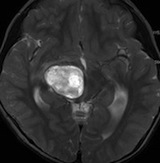

14歳少年の右視床中脳の毛様細胞性星細胞腫です

放射線治療前

生検術の後で48.6グレイ(1回線量 1.8グレイ,27分割)の放射線治療をしました。軽い左片麻痺がありました。テモゾロマイドを併用しています。

pseudoprogression スード・プログレッション

放射線治療の4ヶ月後くらいから腫瘍が大きくなりはじめ,麻痺が悪化しました。画像は放射線治療9ヶ月後のものです。腫瘍は大きくなって,周囲の脳浮腫が悪化して,閉塞性水頭症になっています。この間,大量のリンデロンを使いましたので,ステロイド治療の副作用で肥満になりました。この例のような,のう胞性拡大のようにみえるスードプログレッションは毛様細胞性星細胞腫の放射線治療後に特徴的に生じるものです。

この時点で再燃(再発)と間違って,あわてて危険な開頭手術をしてはなりません!

何にもしないで治ってしまう

我慢に我慢を重ねて,放射線治療後16ヶ月後です。腫瘍は消失しましたし,左片麻痺も良くなって,少年は野球ができるようになりました。

pseudoprogressionのときに腫瘍摘出術をしていたら,重度の障害が残ったでしょう。